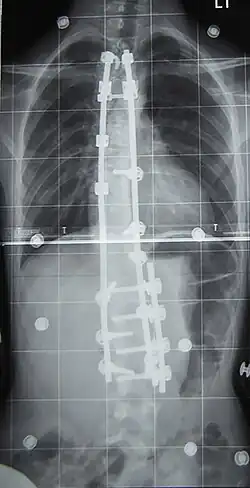

Wanneer de uiteindelijke bocht naar men verwacht boven de 40 à 45 graden uit komt, wordt in principe een operatie geadviseerd. Hierbij heeft men de keuze tussen benadering van de voorzijde (anterior fusion) en van de achterzijde (posterior fusion). Belangrijk is dat niet alleen door het laten versmelten van wervels de zijdelingse bocht wordt gestabiliseerd, maar dat ook de rotatie wordt tegengegaan. Daarom wordt een pen (een zogenaamde Harringtonstaaf, genoemd naar de Amerikaanse orthopeed Paul Harrington) operatief langs de wervels geplaatst en op meerdere plaatsen vastgezet.

Na operatie